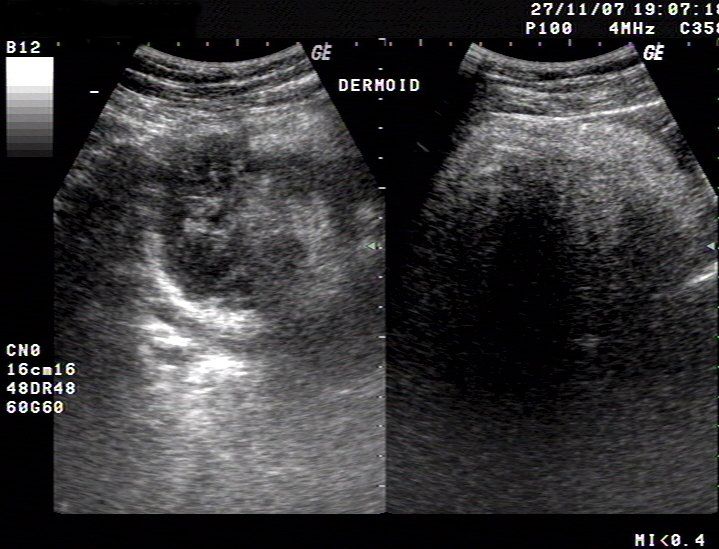

Latest News